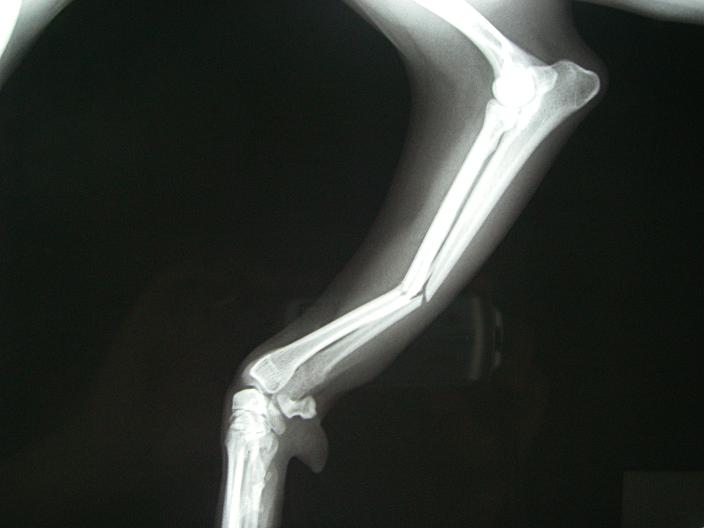

年中無休のいつもの動物病院にタクシーで乗りつけ、レントゲンを撮った所

やっぱり骨折。それも右足、2本でした。

骨折.JPG

2本ともポッキリ

骨折2.JPG

シュカはそのまま入院。もちろん手術しなければなりません。骨を金属のプレートでネジ止め

するそうです。まだ、腫れが治まるまで手術は出来ないとの事。

予定では9/11日の火曜日に手術。入院期間は2~3週間。上手く骨が付けば3ヶ月ぐらいで完治

かな。まだ生後11ヶ月、骨は鉛筆の太さぐらい、体重も6.0キロ。いつももっと高い所から